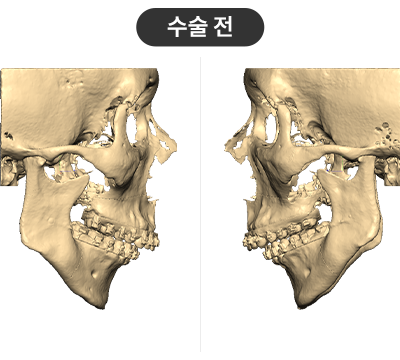

STEP 01

Cutting guide를 이용하여 3D로 계획된 삭제량만큼 뼈를 삭제

STEP 02

Wafer를 이용해 상악의 돌출을 뒤로 교정 무턱의 하악을 앞으로 빼내어 정상교합에 위치시킨 뒤, 맞춤형 Plate로 뼈를 고정

수술결과

무턱 개선 : 턱 끝 기준 17mm 전진